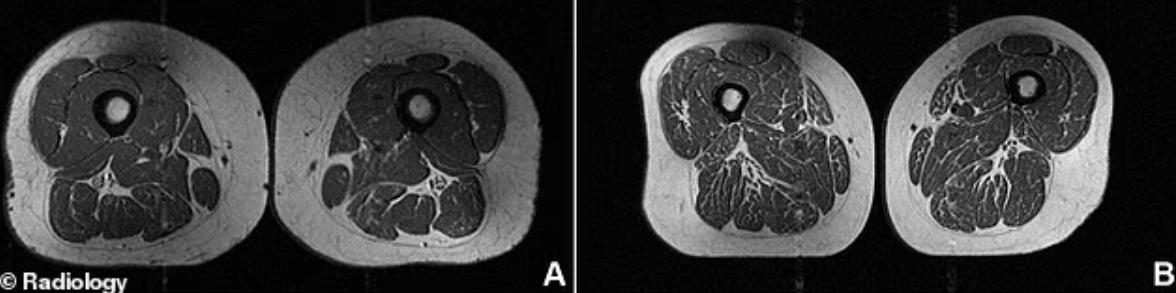

Hình ảnh chụp cộng hưởng từ (MRI) của hai người phụ nữ có độ tuổi và cân nặng tương đương. (A) Một phụ nữ 61 tuổi có chế độ ăn với 30% thực phẩm siêu chế biến. Cơ đùi của bà cho thấy ít bị nhiễm mỡ. (B) Một phụ nữ 62 tuổi có 87% chế độ ăn đến từ thực phẩm siêu chế biến. Đùi của bà trông nhiều mỡ hơn rõ rệt với nhiều vệt trắng thay thế mô cơ khỏe mạnh. Ảnh: Radiology

Trong một nghiên cứu ca lâm sàng gần đây, các bác sĩ công bố ảnh chụp cắt ngang vùng đùi của một phụ nữ 62 tuổi. Hình ảnh cho thấy phần cơ đùi xuất hiện những vệt trắng xen kẽ dày đặc, giống như miếng thịt bò có vân mỡ hơn là mô cơ khỏe mạnh.

Người phụ nữ này hấp thụ tới 87% lượng dinh dưỡng hàng ngày từ thực phẩm siêu chế biến (Ultra-Processed Foods - UPFs). Khẩu phần ăn chủ yếu gồm ngũ cốc ăn liền, thanh chocolate và nước ngọt có ga. Dù vẫn duy trì mức vận động vừa phải, chế độ ăn quá nhiều UPFs vẫn khiến cơ bắp suy giảm rõ rệt.

Trong khi đó, hình ảnh của một phụ nữ khác cùng độ tuổi và cân nặng tương đương nhưng chỉ tiêu thụ khoảng 30% thực phẩm siêu chế biến cho thấy cơ đùi gần như không có tình trạng xâm nhập mỡ.